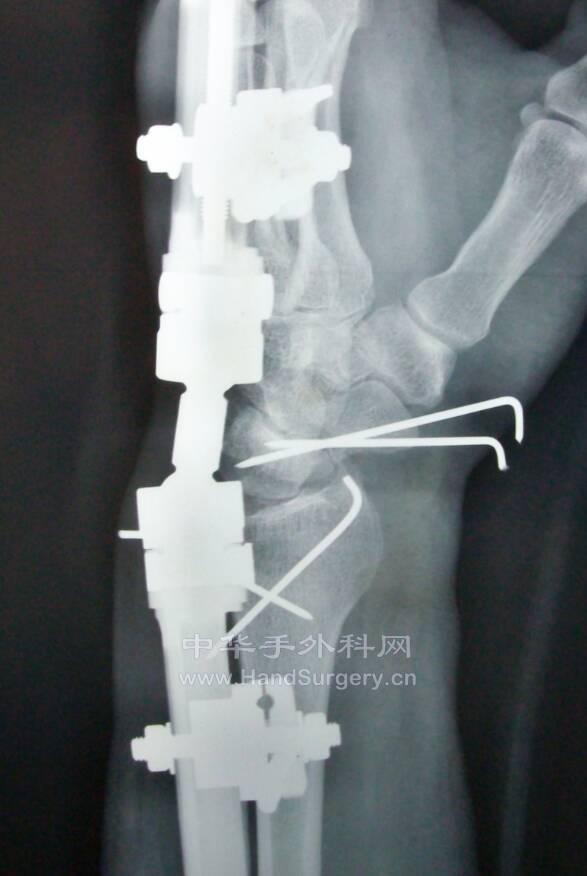

桡骨远端骨折,远端粉碎或太短,不能接受钢板远端钉排

克氏针+外固定支架是绝佳选择

这里就是其中一个典型病例

桡骨远端骨折C3型合并舟骨骨折

有限切开,外固定架的持续牵引,可以利用软组织夹板作用,维持粉碎骨块的复位